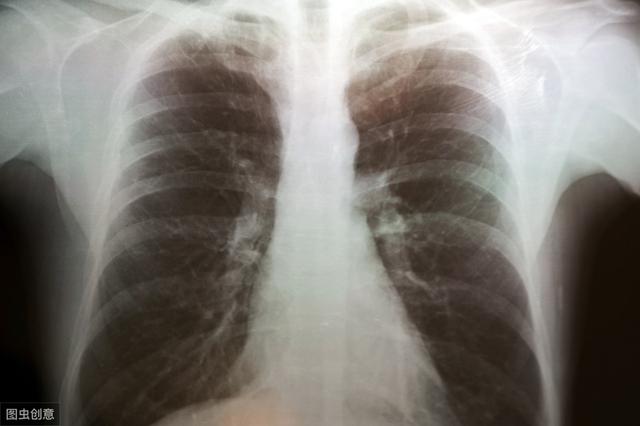

肺气肿来临前,或会先出现3个症状,提醒:55岁后不要忽略肺气肿,作为一种慢性肺部疾病,正在全球范围内威胁着人们的健康。它不仅导致肺功能受损,还可能引发呼吸困难、体力活动受限等一系列严重问题。尤其在55岁及以上的人群中,肺气肿的发病率显著上升,因此,了解肺气肿的早期症状及预防措施显得尤为重要。肺气肿,简单来说,是肺部终...

咳嗽胸闷气短要小心肺气肿,5类因素4个预防措施需知导致肺泡过度膨胀、破裂,最终形成永久性“气球破裂”。肺气肿患者肺部如同“漏气的气球”,呼吸效率逐渐丧失。 肺气肿的“致命链条” 1... 为等待移植患者争取宝贵时间 如何预防? 1. 戒烟的蝴蝶效应 戒烟1年:呼吸道纤毛功能恢复50% 戒烟5年:肺气肿进展风险降低35% 戒烟10年:肺...